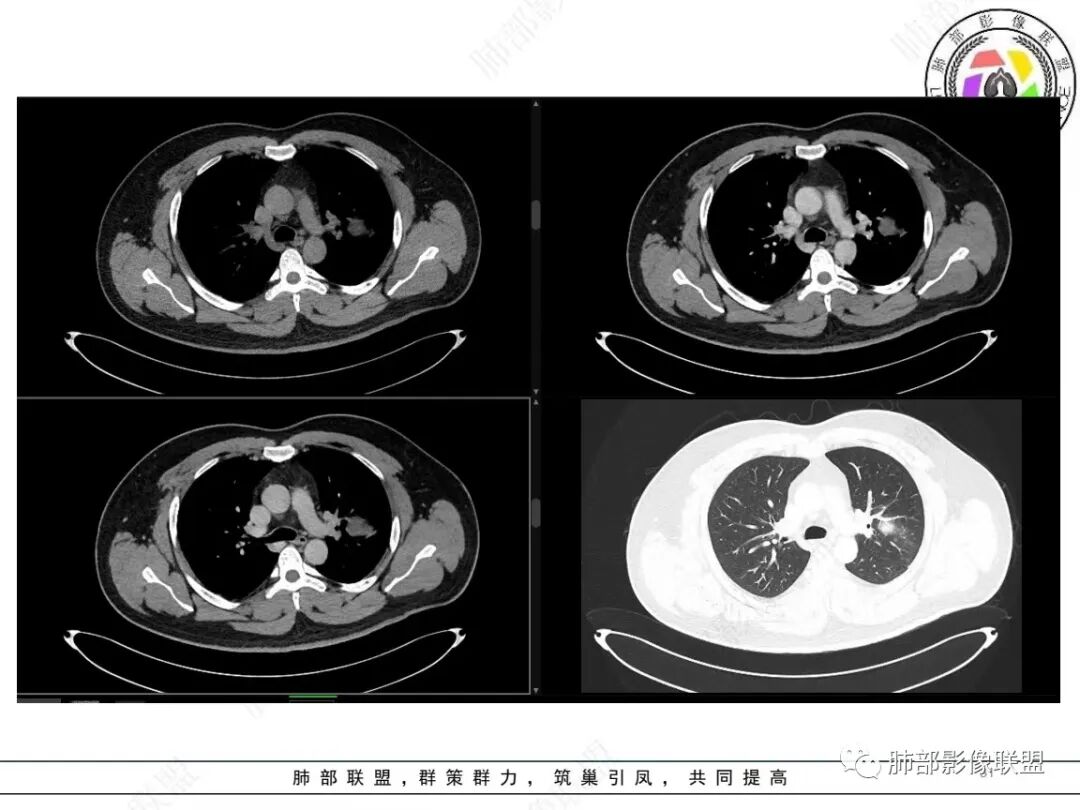

中年人,咳血,左肺上叶实性团块,边界清晰,与胸膜分界不清,可见栽赃表现,病灶推挤支气管及肺血管内移,增强可能条纹血管影,总体强化明显,考虑恶性或交界性肿瘤,间叶组织来源,肉瘤,SFT,肉瘤样癌,滑膜肉瘤。

左肺上叶胸膜肿块,浅分叶,边缘光整,密度不均匀,周围气管及血管受压推移,边缘强化,考虑肉瘤,鉴别SFT

左肺上叶占位,平扫密度较低,临近胸膜栽赃桩,外向内生长,边缘有膨隆、毛糙,增强后轻度强化,边缘弧线样强化,考虑肉瘤样癌

左上肺软组织肿块,周围散在磨玻璃影,界不清,窄基底贴于胸壁,胸膜下脂肪间隙不清,呈低强化,胸膜下见。与主病灶强化方式一样的病变,2R区见肿大淋巴。考虑恶性,间叶组织来源合并出血。

青年男性,咯血;CT示左肺上叶胸膜下软组织肿块,边界尚清,宽基底与胸膜相连,增强动脉期内见细条状血管影,轻度延迟强化,定位:肺外,胸膜外脂肪存在,考虑脏层胸膜起源;定性:考虑SFT。

影像表现:左肺上叶占位合并出血,胸膜栽赃,边缘强化,局部见血管影,中心密度20Hu,无强化,符合非液化坏死。定位:肺内,定性恶性(明显血管影,栽赃排除错构瘤,中心无强化排除PSP,无明显清楚的坏死边界,强化不符合肉芽肿,排除结核),年龄轻,无长时间吸烟史和肺气肿改变,肉瘤样癌可能性很小,与支气管无确切关系,所以病理类型考虑来源于肺间叶组织的肉瘤,骨外尤文?滑膜肉瘤?

有血供,强化不明显,周围肺出血,肺组织受压改变,定位肺外,胸膜增厚,部分胸膜下脂肪间隙存在,不确定肋骨是否受侵犯,部分层面与肺动脉分界不清,感觉推移,如果供血要考虑sft,强化不符合,有血管进入,但是强化不明显,密度相对均匀,所以不考虑坏死,富含粘液可能,咯血,说明累及支气管了,有一定侵袭性,肿块大,考虑间叶来源肿瘤,与胸膜接触面相对不是宽基底,综合考虑滑膜肉瘤可能,典型的滑膜肉瘤一般铺路石改变,这个又觉得信号相对均匀了一些学习中